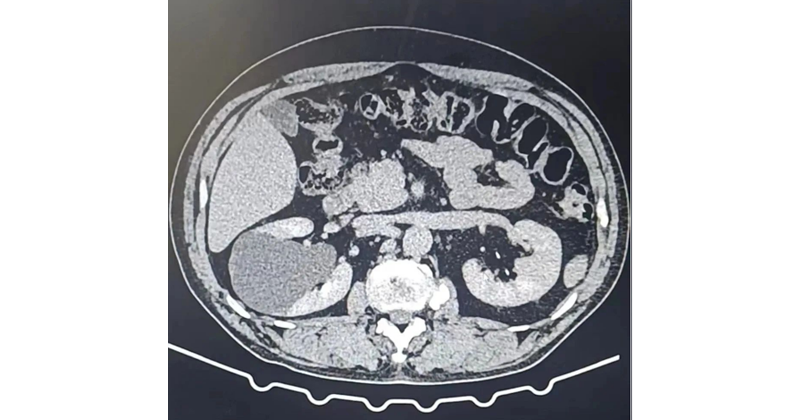

(2) CT對(duì)B超檢查不能確定者有價(jià)值。囊腫伴出血或感染時(shí),呈現(xiàn)不均質(zhì)性,CT值增加。當(dāng)CT顯示為囊腫特征時(shí),可不必再作診斷性穿刺。

1. 腎積水:是由于腎盂、輸尿管梗阻造成腎臟產(chǎn)生的尿液不能排至膀胱,導(dǎo)致腎盂或者腎盞擴(kuò)張積水(尿液),合并感染可有腰部酸痛,IVU檢查及逆行腎盂造影顯示腎盂腎盞擴(kuò)大;B超、CT檢查示腎中心部液性暗區(qū),腎實(shí)質(zhì)變薄;腎圖呈梗阻曲線。

2. 多囊腎:主要表現(xiàn)為腹部不適、腹部腫塊,偶見(jiàn)血尿。B超和CT見(jiàn)腎實(shí)質(zhì)內(nèi)囊性腫塊。但囊腫內(nèi)部被分隔成多個(gè)液性暗區(qū)。